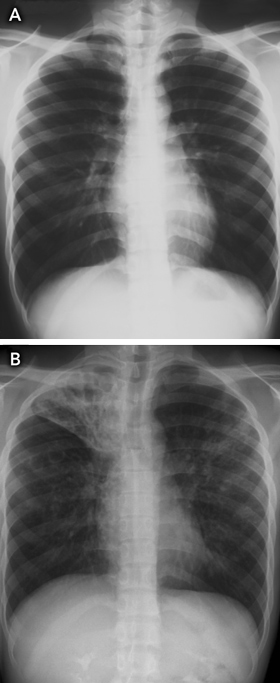

As the median time between arrival in Australia and notification of TB was 2 years (indicating that some patients may have arrived with active TB), another strategy that might improve TB control is pre-departure screening for active TB, particularly in resource-limited settings. For example, the Australian Government Department of Immigration and Citizenship could develop guidelines for countries performing pre-migrant screening that outline minimum laboratory standards for TB culture testing for applicants with abnormal chest x-ray findings. Unfortunately, this strategy would still not detect most people entering Australia who have latent TB and normal chest x-ray findings when they obtain their visa (Box 6).